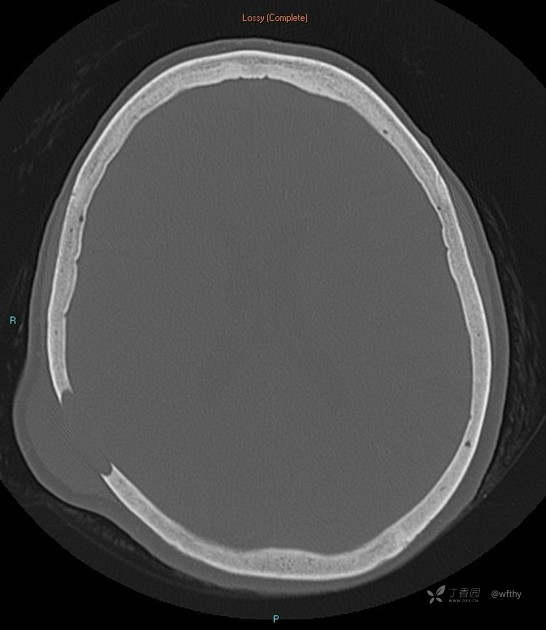

病例女65,头部肿块